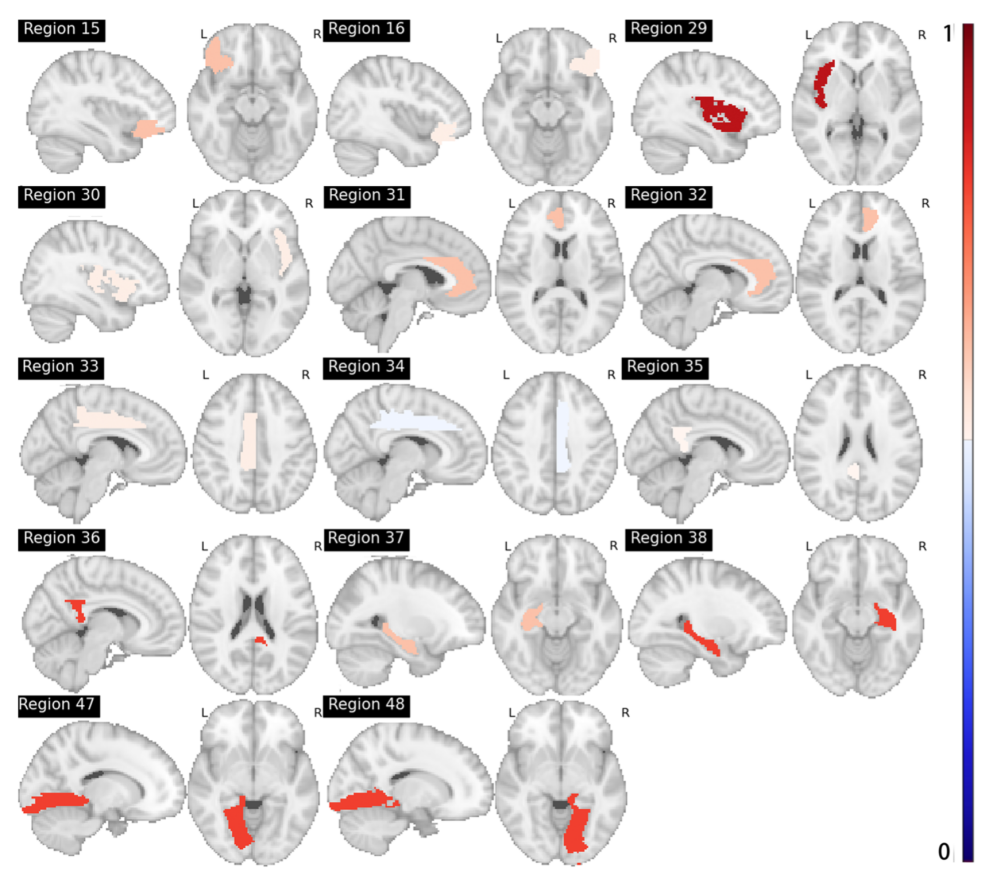

在辅助神经调控方向,以大数据AI算法寻找脑康复重要脑区与脑环路,是实现精准神经调控的关键。通过AI深度学习寻找阿尔兹海默症的认知康复的重要脑区靶点,根据功能磁共振的脑影像数据,找到90个标准脑区中最重要的14个认知康复脑区,为后续精准神经调控奠定了基础;利用这些重要脑区研究脑卒中神经调控康复过程中的近红外大数据,通过AI深度学习建立近红外数据的康复有效性评价模型,进而形成最优化调控方案。